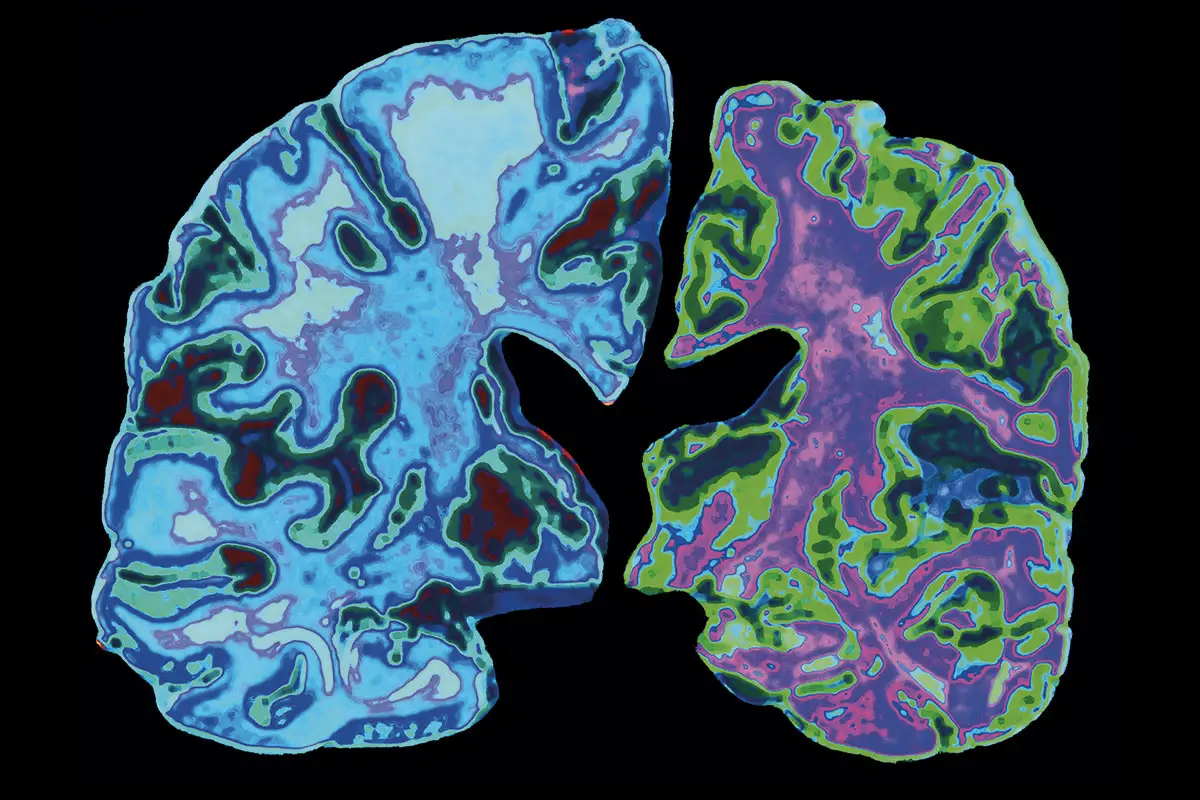

Alzheimer's is an immune system disorder, doctor says

For years, scientists have been focused on trying to come up with new treatments for Alzheimer's by preventing the formation of brain-damaging clumps of a mysterious protein called beta-amyloid. But is that really the key to the disease? In July 2022, Science magazine reported that a key 2006 research paper, which identified beta-amyloid as the cause of Alzheimer's, may have been based on fabricated data. Other scientists believe there may be other causes: Donald Weaver, who runs the Krembil Brain Institute in Toronto, says his research shows that Alzheimer's may be an immune system disorder. "We believe that beta-amyloid is not an abnormally produced protein, but rather is a normally occurring molecule that is part of the brain's immune system," he writes.